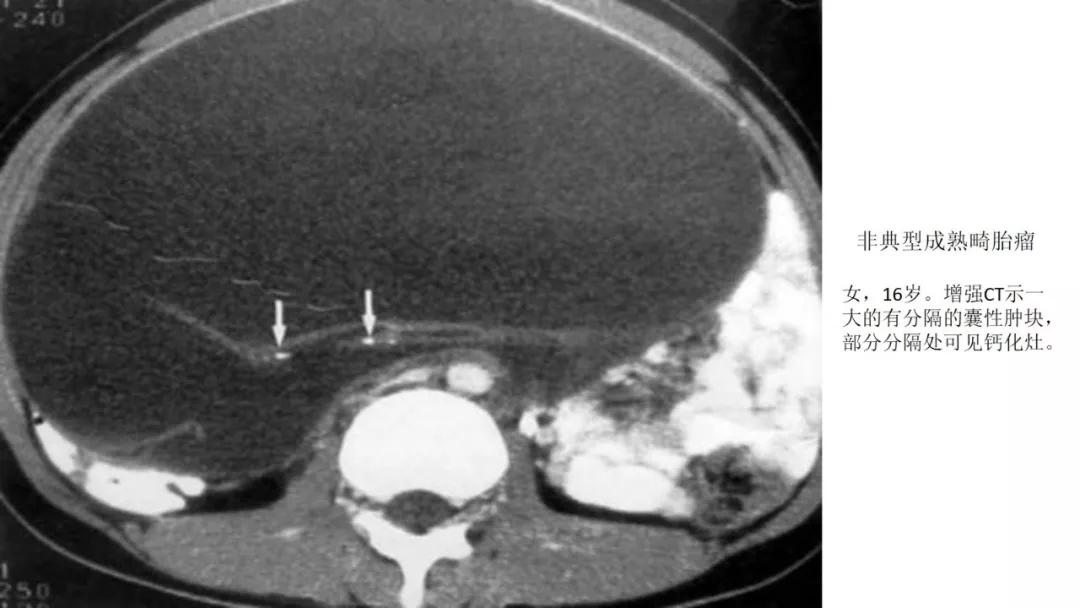

生殖细胞肿瘤占卵巢肿瘤的20%,以成熟畸胎瘤-皮样囊肿多见,良性多,恶性少。表现为囊实性混合性或实性肿块,大多数含有脂肪、钙化等特征。

良性者常呈囊性肿块,脂囊,脂液囊,液囊。少数混合成分,实性。壁光整可稍厚,囊内有脂、液分层现象,多数伴有粗大钙化或骨骼。